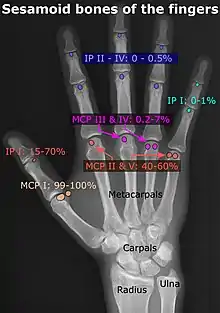

- In the hand—two sesamoid bones are commonly found in the distal portions of the first metacarpal bone (within the tendons of adductor pollicis and flexor pollicis brevis). There is also commonly a sesamoid bone in distal portions of the second metacarpal bone.